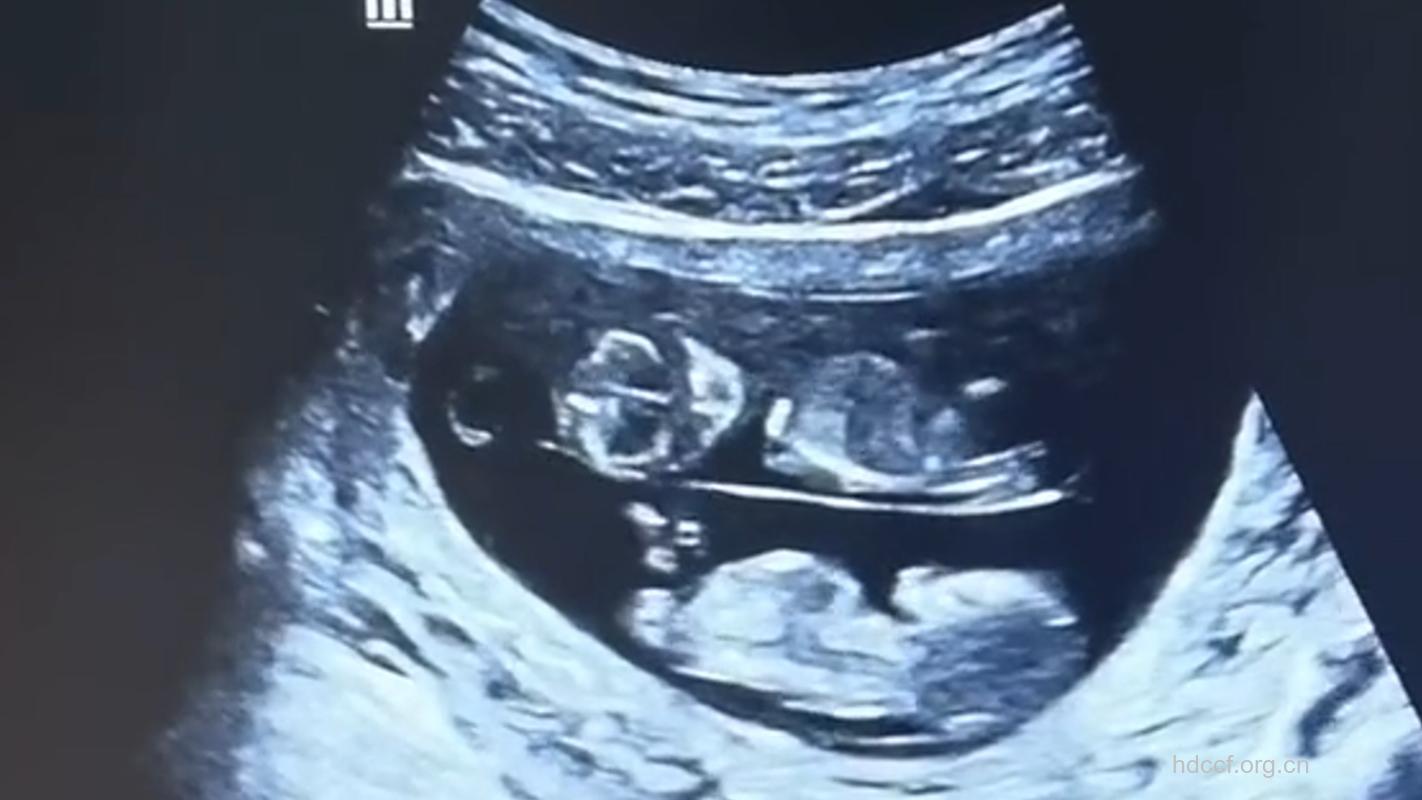

一般在孕18—22周之间,需要做一次B超,那么孕妈妈这一周就可以去做了。 正常情况下,B超在孕早期做1次,孕中期做1次,孕晚期做1次。3次的目的各不相同:早期了解孕龄,中期了解胎宝宝发育有无异常,晚期了解胎宝宝大小及是否安全。如果有特殊情况,如羊水过少的准妈妈,要观察她们经过治疗后是否改善,那就应在治疗后7—10天复查,因此B超检查的频率应由医生来决定。